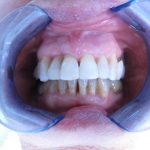

Présentation cas clinique :

Avant traitement

Après traitement